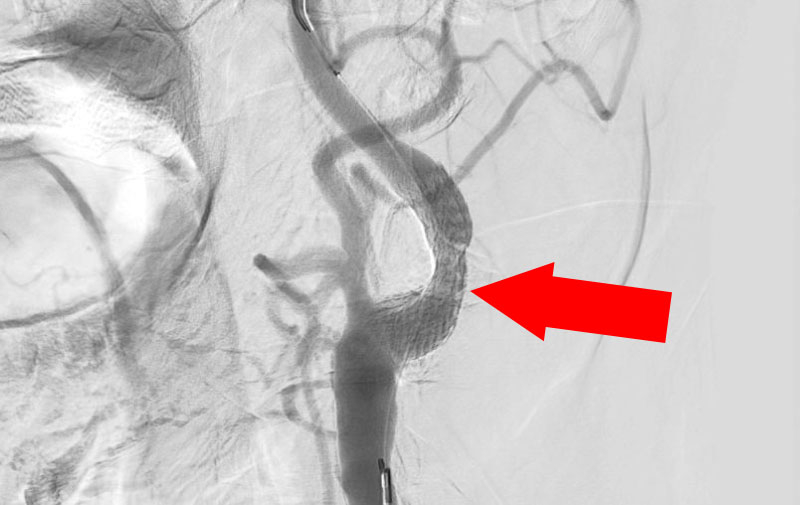

'21年12月

左内頚動脈脳動脈瘤

80代

大阪府の病院

No.1162 手術前

No.1162 手術中

No.1162 手術後